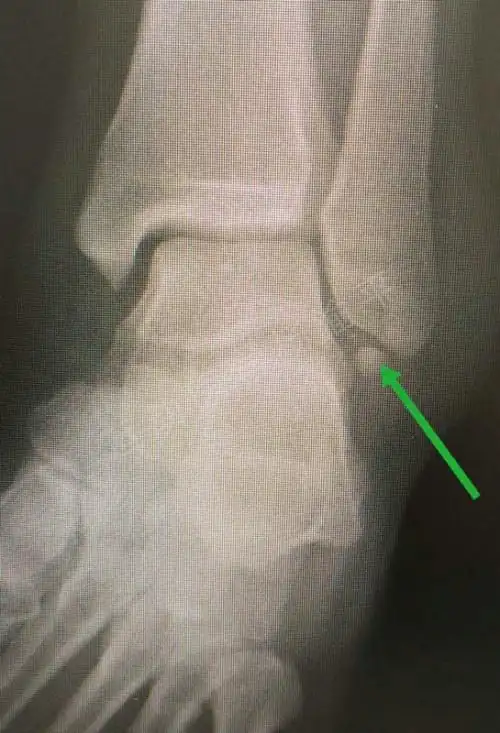

外踝扭伤撕脱骨折的手术知识清单